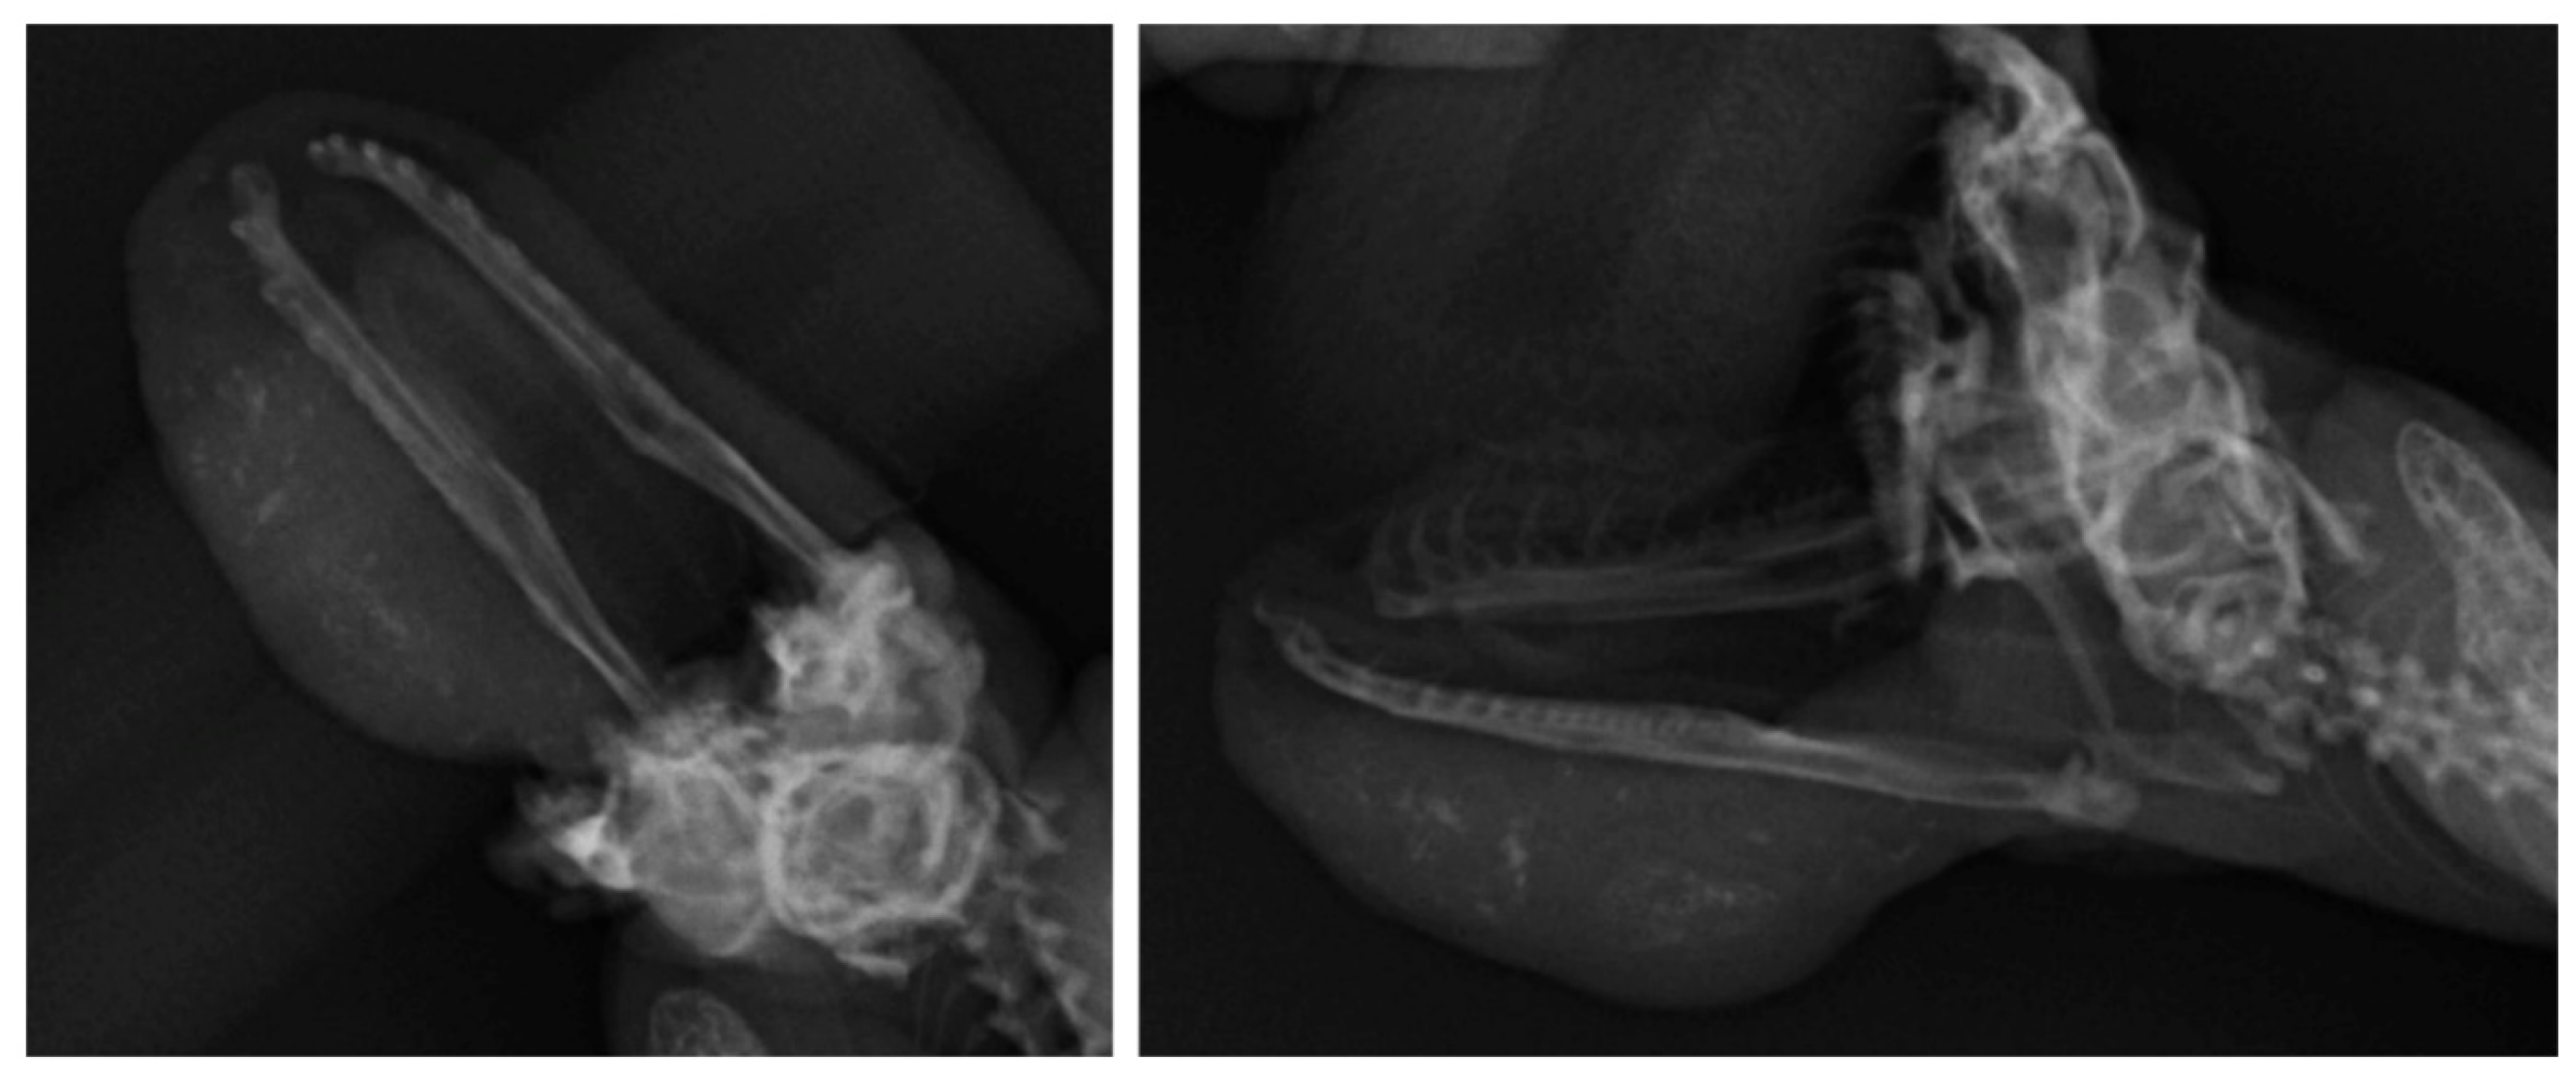

A Case of Submandibular Leiomyosarcoma, Mimicking an Abscess, in a Ball Python (Python regius)

2. Case Presentation